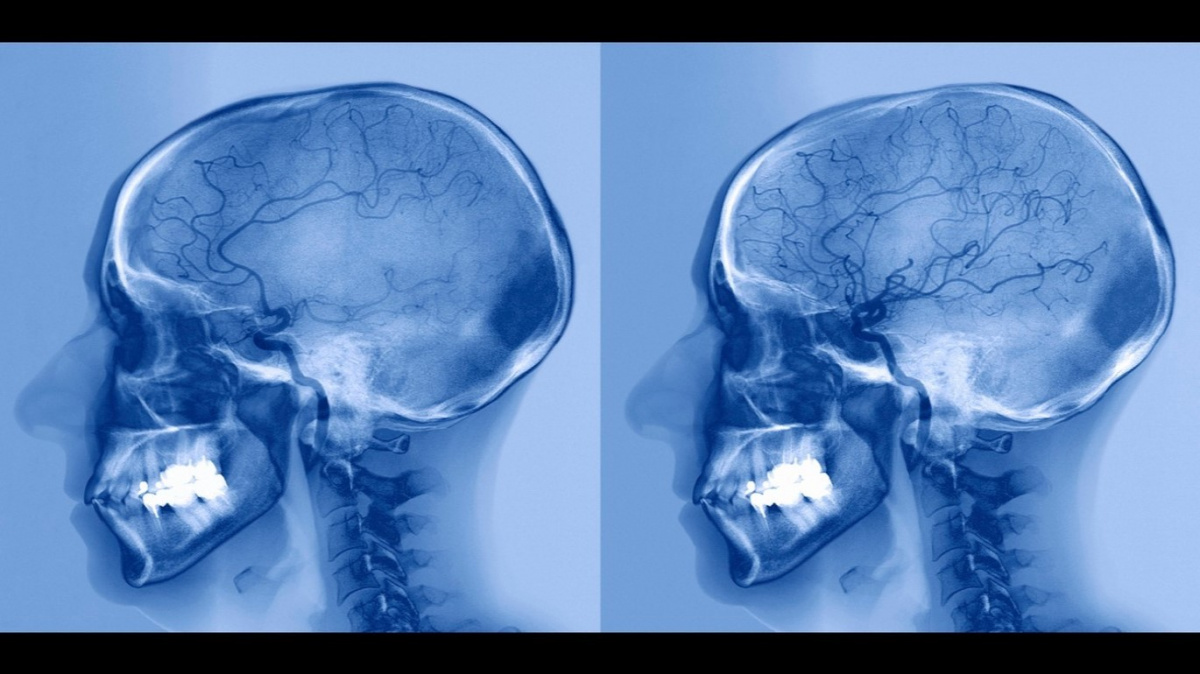

Rentgen tepen mozku pacienta před (vlevo) a po (vpravo) léčbě mrtvice, která nastala kvůli zablokované mozkové tepně. Důsledkem byl nedostatek průtoku krve do střední části mozku.zdroj: Profimedia

Neurovědci z Londýnské univerzity (UCL) v novém výzkumu upozorňují, že koronavirus může způsobit neurologické komplikace, včetně mrtvice a fatálního zánětu mozku.

Osm pacientů ve sledovaném vzorku – nejmladší byla sedmadvacetiletá žena – prodělalo mozkové mrtvice vlivem krevních sraženin. U další studované pacientky se po (předešlém) propuštění z nemocnice vyvinula halucinace. Žena viděla po svém domě pobíhat lvy a opice. Poté si vyvinula Capgrasův syndrom, u nějž se pacient domnívá, že všechny jeho blízké nahradili identičtí dvojníci.